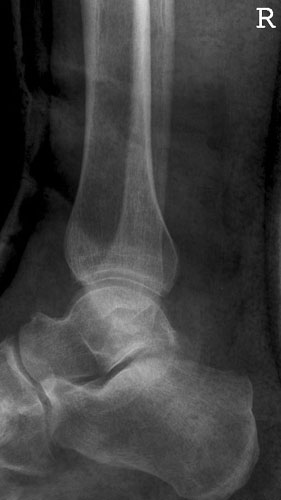

OSG seitlich

132_3.jpg

Fehler

Doppelkonturierung im vorderen Teil der Talusrolle. Die Fibula ist gegen dem Malleolus internus nach ventral verschoben. Die Längsachse des Talus ist verkürzt. Das untere Sprunggelenk kann nicht beurteilt werden.

Abhilfe

Keilkissen unter den Calcaneus legen bzw. Fuß flacher auf den Zehen auflegen lassen.